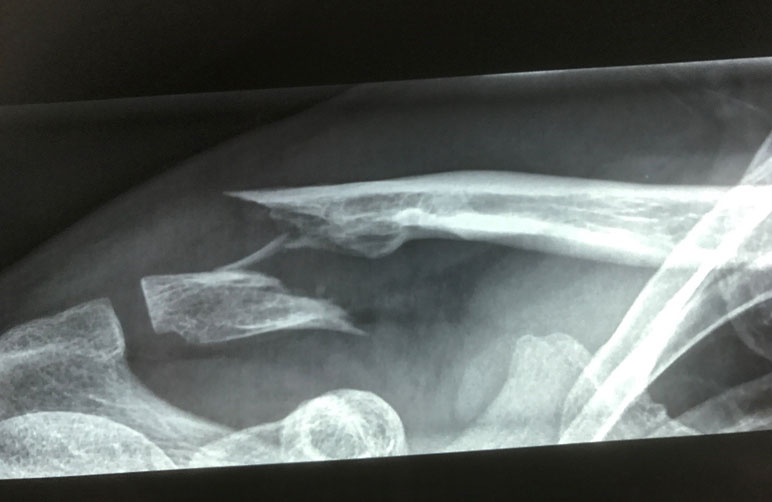

What do clavicle fractures look like on X-ray?

Below are examples of typical fractures that benefit from surgery.

Click an image to enlarge